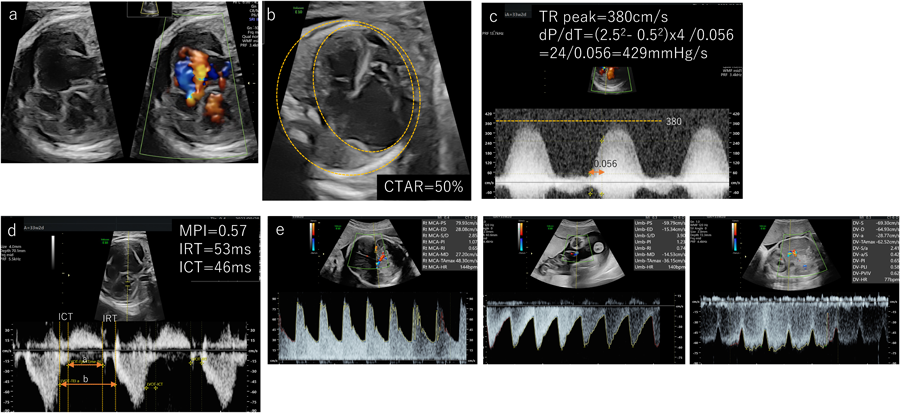

Ebstein病(Fig. 9)

Ebstein病は三尖弁の中隔尖の下方付着により,三尖弁逆流に伴う右房拡大や右心負荷が胎児期より問題となり,胎児水腫を来すリスクの高い先天性心疾患(Fig. 9a)である.海外ではNSAIDsを使用した胎児治療も報告されている24)が,本邦では胎児治療の適応に至っていない.胎児治療を検討する可能性のある疾患として,胎児心機能を評価することは重要である.心拡大CTARの評価(Fig. 9b)は言うまでもないが,三尖弁逆流の最大血流速度を計測し,心室圧を推定することで右室の残存する心機能を評価する.dP/dtはCVPSにも使用されているが,収縮能を反映する(Fig. 9c).簡易ベルヌーイの式から算出され,dP/dt=(2.52–0.52)×4/時間(秒)=24/時間(秒)で求めることができる.正常値は800 mmHg/s以上であり,400 mmHg/s以下は重度の収縮不全があると考える25).2023年に本邦からの報告で,dP/dT≧350 mmHgかつ三尖弁逆流最大血流速度≧2.9 m/sでは出生後の両心室修復を予測できるとしている26).また拡大した右房による圧迫で左室機能不全を来すこともあるため,左室のMPIを評価(Fig. 9d)することが有用とする報告もある.Ebstein病の予後予測を評価する報告は散見され,TorigoeらはMPIと三尖弁逆流の最大血流速度を取り入れたTRIPP scoreの有用性も提示している27).また動静脈ドプラ(Fig. 9e)では臍帯動脈の途絶や逆流,臍帯静脈血流の減少は独立した周産期予後に影響を与える因子として提示されている28)

Pediatric Cardiology and Cardiac Surgery 40(2): 103-112 (2024)

Fig. 9 Ebstein病の一例

TR=三尖弁逆流.CTAR, cardiothoracic ratio; ICT, isovolumetric contraction time; IRT, isovolumetric relaxation time; MPI, myocardial performance index